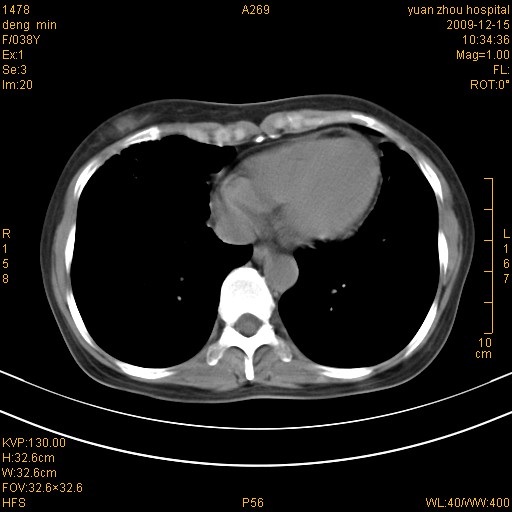

标题: CT23919:F38Y 咳嗽月余 [打印本页]

标题: CT23919:F38Y 咳嗽月余

支扩并感染

右肺中下叶、左肺上叶舌段及左肺下叶支气管扩张合并感染。